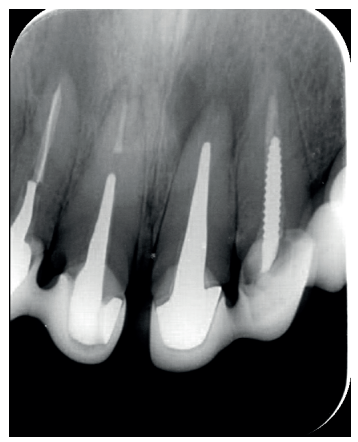

El paciente aporta como estudio radiológico una ortopantomografía (OPG), (Figura 1). Se realizaron radiografías periapicales (Figuras 2 y 3), así como exploración clínica incluyendo la valoración periodontal de los dientes afectados, sin observar profundidades de sondaje aumentadas que pudieran indicar la existencia de lesiones endoperiodontales.

Para confirmar el origen endodóntico y el tamaño de las lesiones se realizaron exploraciones tomográficas con espesor de corte de 75 micras mediante CBCT CS8100 (Carestream Dental® ) en las que se evidenciaron lesiones periapicales radiolúcidas a nivel de 12, 11, 21 (con afectación bicortical), 25 y raíces vestibulares de 26 (Figuras 4 a 8).

Para el correcto diagnóstico de lesiones radiolúcidas a nivel periapical es importante disponer de imágenes radiológicas que muestren con precisión la situación y tamaño de dichas lesiones. En nuestro caso el paciente aportaba una ortopantomografía. Este tipo de radiografía no es adecuada para el diagnóstico en endodoncia. La radiografía periapical aporta mejor definición, especialmente a nivel anterior, ya que presenta una menor distorsión. Actualmente el CBCT es la prueba radiológica más fiable, ya que proporciona imágenes en las tres dimensiones del espacio, lo que permite diagnósticos más precisos1,2 .